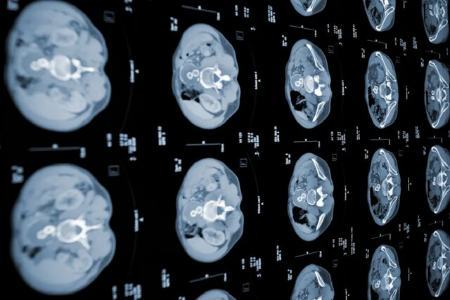

به گزارش ایسنا به نقل از انگجت، پژوهشگران موسسه فناوری ماساچوست (MIT) که بر مهندسی رایانه و توسعه هوش مصنوعی تمرکز دارد، دو الگوریتم یادگیری ماشینی ساختهاند که میتواند سرطان لوزالمعده را زودتر از استانداردهای تشخیصی فعلی تشخیص دهد.

این دو مدل هوش مصنوعی جدید با هم برای ایجاد یک شبکه عصبی موسوم به PRISM و تشخیص آدنوکارسینوم مجرای لوزالمعده (PDAC) که شایعترین شکل سرطان لوزالمعده است، طراحی شده و شکل گرفتهاند.

معیارهای استاندارد غربالگری PDAC در حال حاضر حدود ۱۰ درصد موارد را در بیمارانی که توسط متخصصان معاینه میشوند، تشخیص میدهد. این در حالی است که مدل هوش مصنوعی جدید MIT توانست موارد PDAC را در ۳۵ درصد مواقع شناسایی کند.